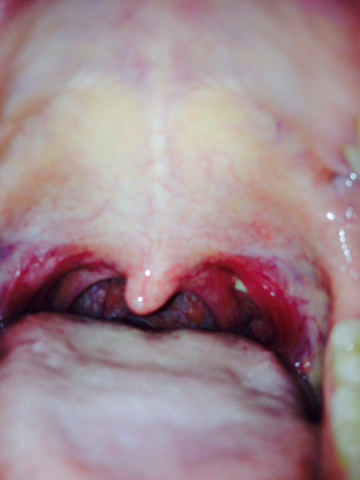

什么是咽后壁溃疡

咽后壁溃疡,也称为咽后壁糜烂或咽后壁疼痛性溃疡,是指发生在咽后壁的炎症性或溃疡性病变。这种状况通常会引起咽部的不适、疼痛、吞咽困难等症状。咽后壁溃疡可能是由于多种原因引起的,包括感染、创伤、过敏反应或自身免疫性疾病等。